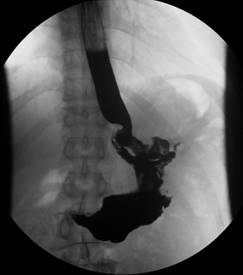

患者杨XX,男,42岁、BMI25.5,因“解黑便伴头昏、乏力1+月”于普外一科住院。伴有心慌、乏力、气促,面色、甲床、睑膜苍白。检查提示胃底贲门巨大肿瘤伴出血,重度贫血。患者胃肿瘤约拳头大小,位于胃底贲门处,距贲门较近。术前全科讨论、患者肿瘤大、距离贲门近,无法行肿瘤楔形切除,拟定行近端切除、残胃保留、双通道吻合。

腹腔镜术中探查证实肿瘤位于贲门口,肿瘤巨大,无法行楔形切除,遂行开腹近端胃切除、残胃保留、双通道吻合。手术顺利,术后患者恢复佳。目前患者以近流食、进食后无腹痛、腹胀、恶心、呕吐、吞咽困难,无返酸、嗳气、烧心、胸骨后烧灼样刺痛等不适。

术后病检回示胃底贲门巨大胃间质细胞瘤、中度侵袭危险性。